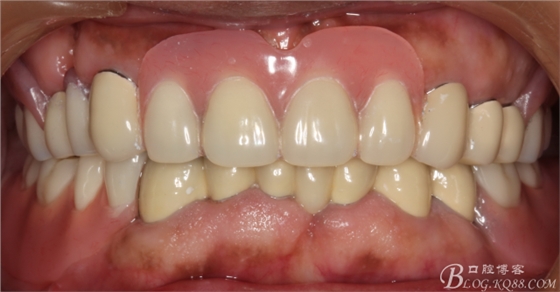

修復(fù)后效果圖,

說(shuō)到咬合重建確是一個(gè)很復(fù)雜的命題,他需要醫(yī)生有很厚的修復(fù)功底,對(duì)待患者的咬合有一個(gè)正確的評(píng)價(jià),根據(jù)經(jīng)驗(yàn)對(duì)垂直患者的咬合距離得以正確的回復(fù)和重建。這個(gè)病例就是對(duì)原來(lái)的垂直距離抬高了2mm,修復(fù)后患者感覺(jué)非常舒服。